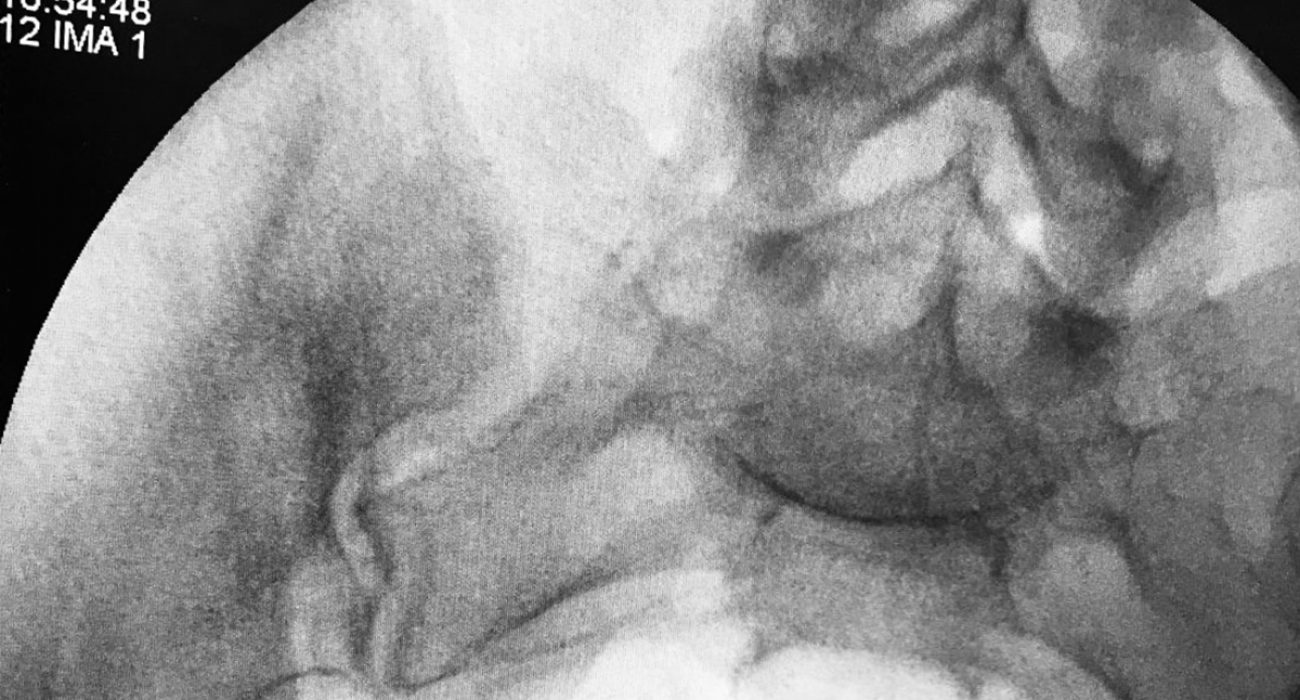

אחת הבדיקות הראשונות אותן תתבקשי להשלים במסגרת בירור אי פריון היא צילום רחם – בדיקה אבחנתית וטיפולית (אחריה יש דיווחים על השגת הריונות), המאפשרת הדגמת חלל הרחם והחצוצרות על ידי הזרקה של יוד לחלל הרחם בעזרת רנטגן.

החומר עצמו מתפזר בחלל הרחם, בחצוצרות ובאגן, ומדגים בצורה טובה את מבנה הרחם, את מעבר החומר בחצוצרות ובהמשך את פיזורו באגן.

בסיום הבדיקה את מקבלת דיסק עם תמונות וסיכום הרופא המבצע בזמן אמת, כלומר, ניתן להתרשם באופן מיידי ממבנה הרחם ותקינות החלל, ואם קיימת חסימה חצוצרתית כלשהי או הידבקויות באגן.